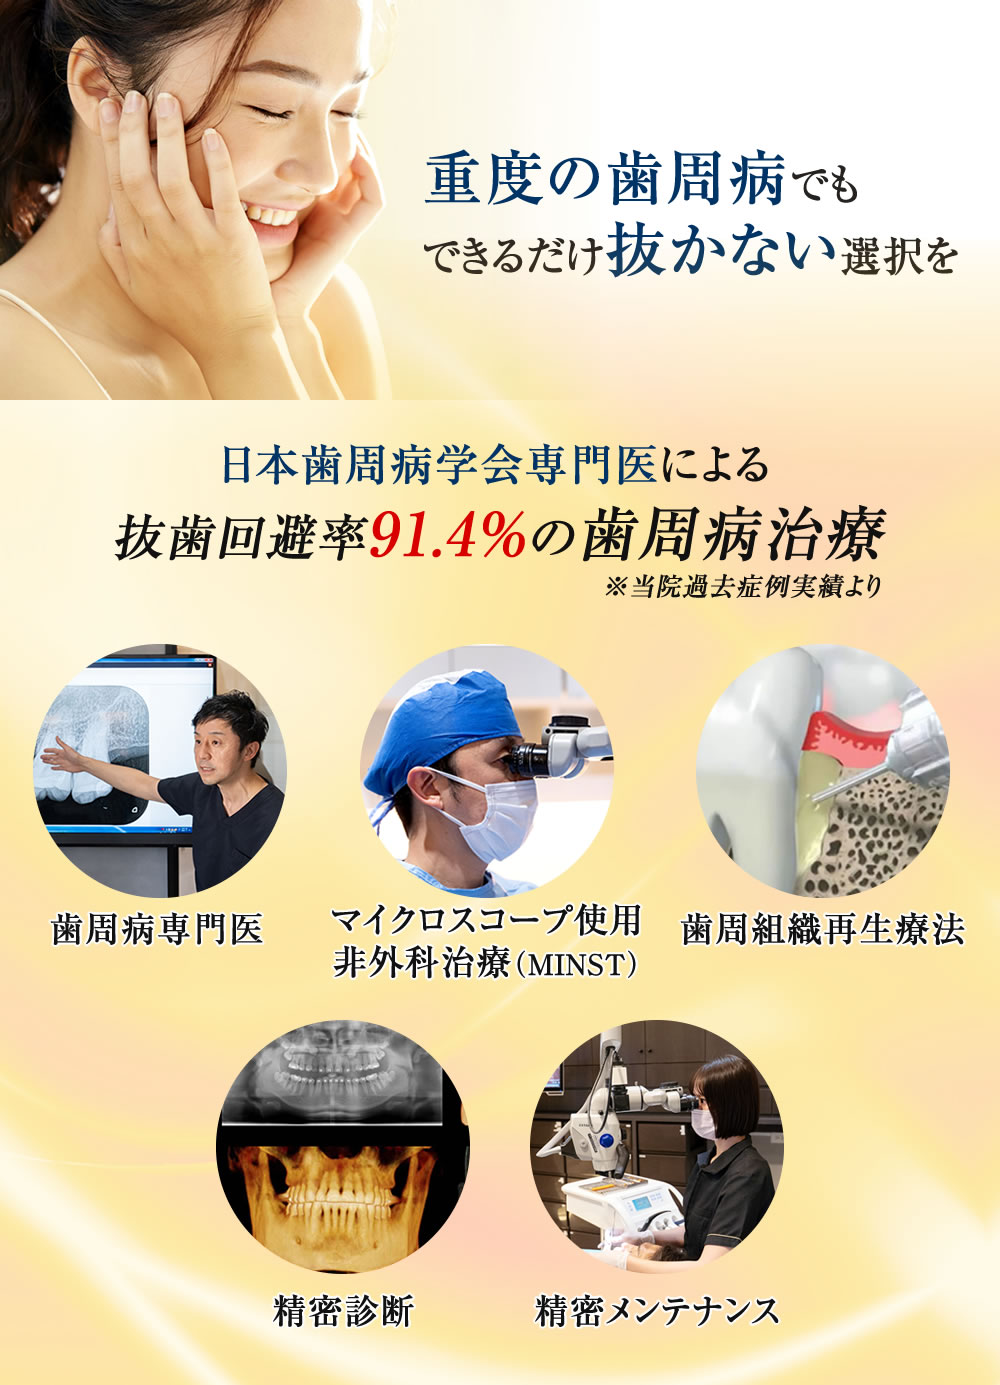

日本歯周病学会専門医による歯周病治療(重度歯周病治療に対応)

BiVi歯科・矯正歯科では、日本歯周病学会専門医が在籍し、抜歯リスクの高い重度歯周病の治療に対応しております。できる限り歯を残すことをモットーに、精密な診断のもと適切な治療計画をご提案いたします。

当院には歯周病の専門医が在籍しているため、埼玉県八潮市のみならず全国より重度歯周病が原因で歯がグラついている方、もしくは他医院で抜歯を勧められた方が相談にお見えになります。全てではありませんが、比較的多くの方が抜歯を回避することができています。

その理由として歯周病治療の成功率が一般の歯科医院に比べて飛躍的に高い(抜歯回避率91.4%!)ことが挙げられると思います。なぜ抜歯回避率が高いのか、8つの観点からご説明いたします。

BiVi歯科・矯正歯科では歯周病を専門に学ぶ学会であり、重度歯周病治療の名医の集団である「日本歯周病学会」の専門医認定を受けた歯周病治療のスペシャリストである歯周病専門医が担当いたします。

「抜かずに残す歯周病治療」に徹底的にこだわって15年、歯がグラグラしている、他医院様で抜歯を宣告された方、重度歯周病治療の名医をお探しの方はぜひ無料相談にお越しください。

当院の歯周病治療は、マイクロスコープを用いた低侵襲非外科治療(MINST:Minimally Invasive Non surgical Therapy)を専門としております。

しかし、近年ではマイクロスコープと小型の清掃器具を併用することにより、歯ぐきを切ったり、痛みを伴ったりすることなく、歯周ポケットの奥深くに付着した歯石の確認、除去が可能となりました。患者さまの負担を抑えながら、より効率よく歯周病の改善が期待できます。